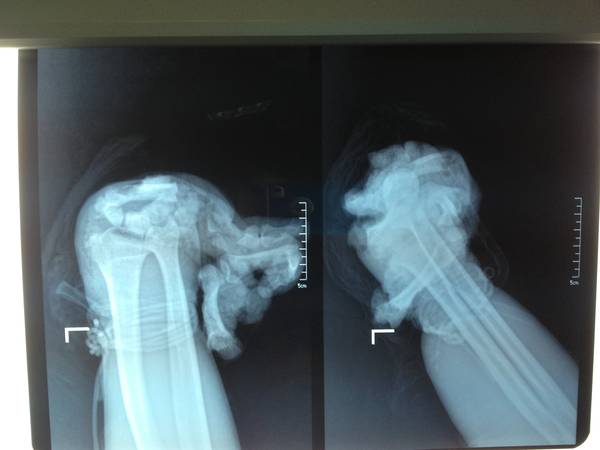

请问老师这种截肢需要注意哪些问题啊    下尺桡关节怎么样处理好啊    需要固定不?谢谢

保留近排腕骨的截肢